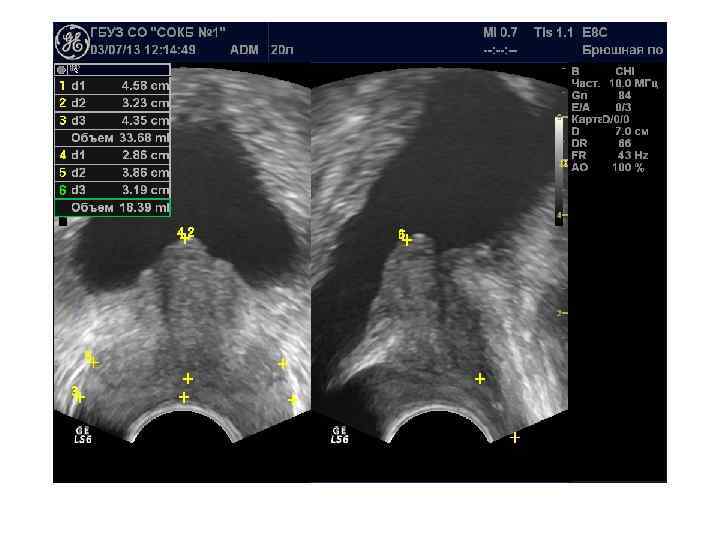

При ТРУЗИ объем простаты может быть определен с помощью нескольких методов: 1. Объем =А х В х С х 0, 52 (рис. 6. 5 А), где А — продольный размер, В — переднезадний размер, С — поперечный размер. Поперечный размер железы определяется при поперечном сканировании в ее средней части, переднезадний и продольный размеры — при сагиттальном сканировании 2. Объем = С 2 х В х 0, 52 где В — передне-задний размер, С — поперечный размер. 3. Объем = С 3 х 0, 52 где С — поперечный размер.

При ДГПЖ меняются форма, размеры, структура и соотношение частей железы. Форма становится шаровидной или неправильной с выбуханием контура в просвет мочевого пузыря. При росте переходных зон происходит значительное увеличение размеров, но это не приводит к выраженной обструкции уретры. При росте периуретральных желез простата увеличена незначительно, но происходит сдавление уретры выбухающей средней долей. Структура гиперплазированных узлов неоднородная, часто с дегенеративными изменениями ( кисты, участки склероза, кальцификаты).